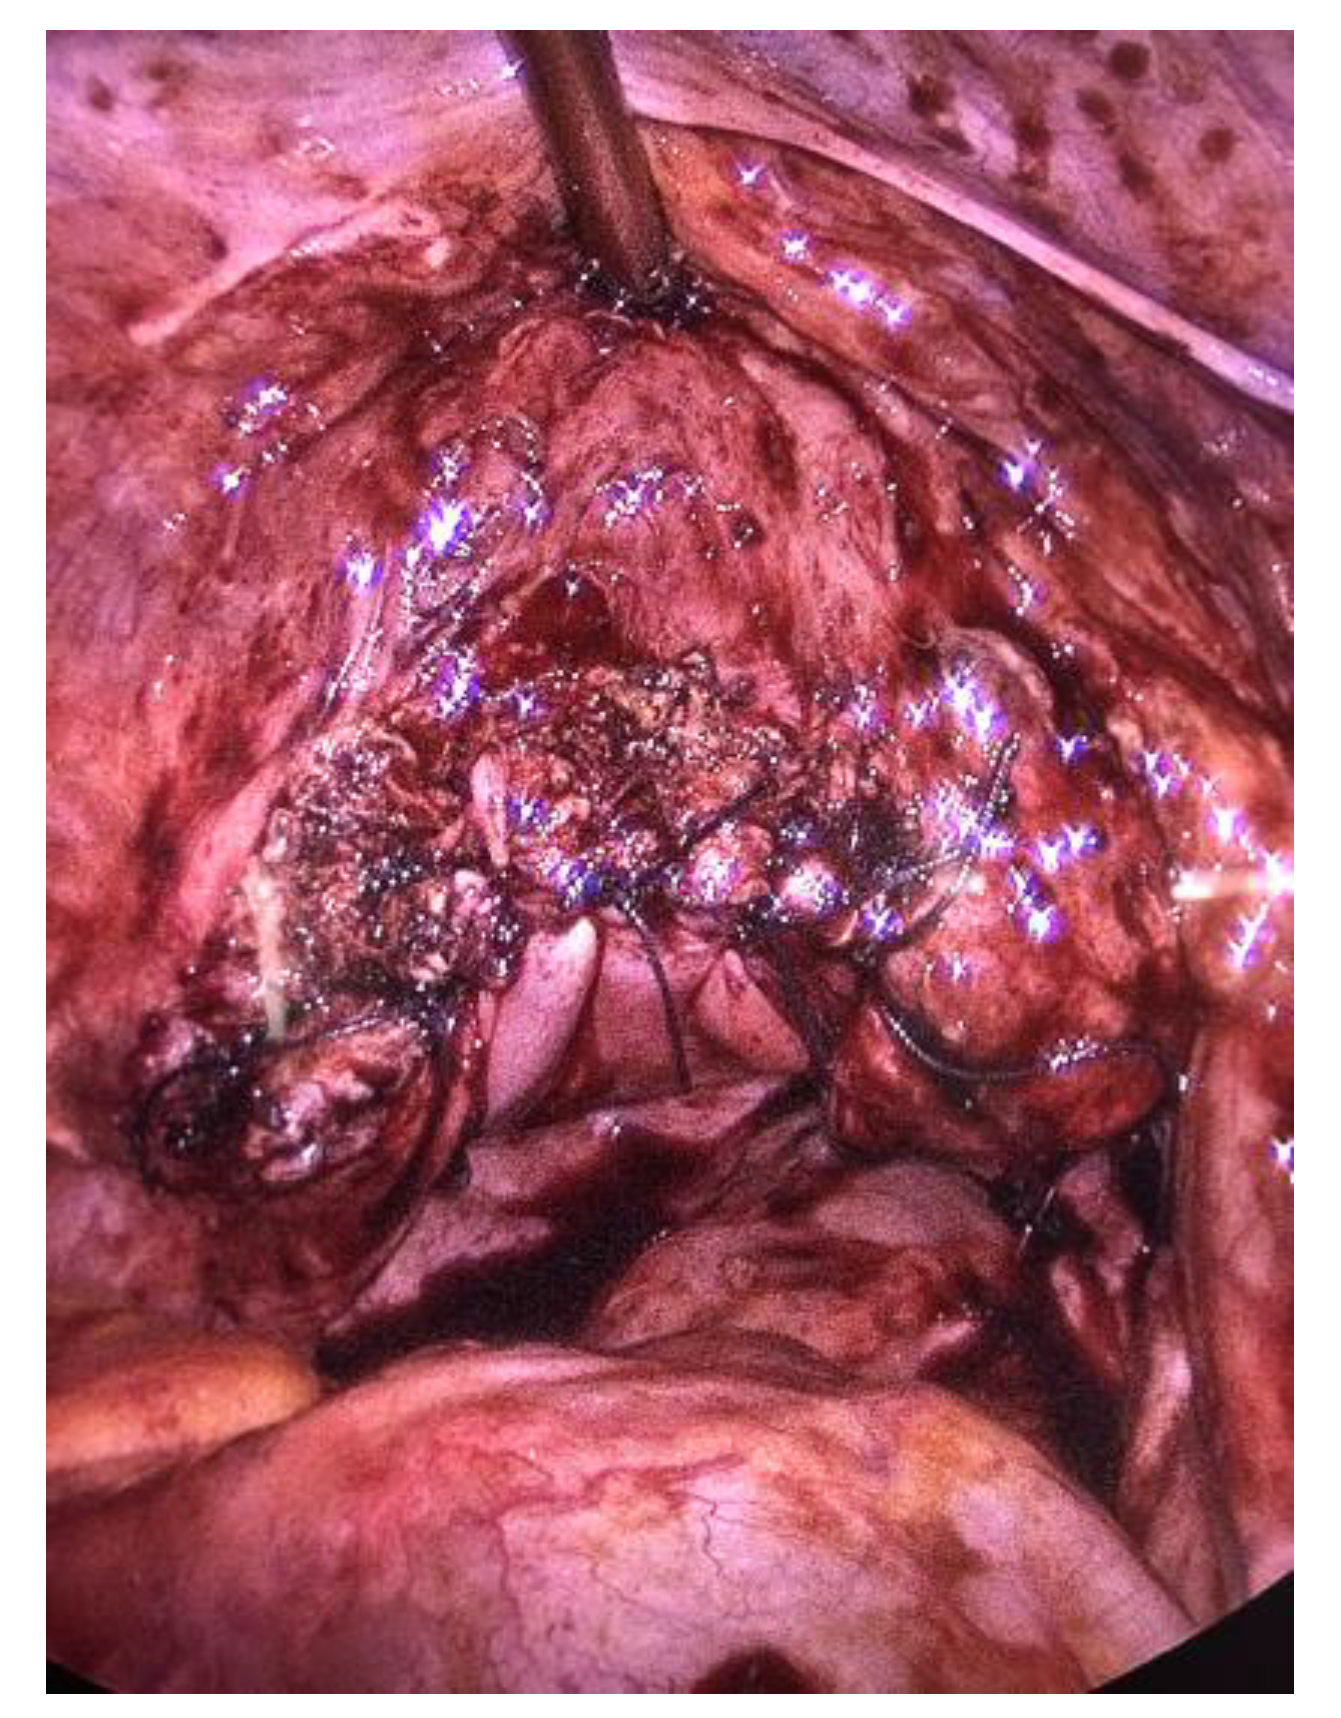

2.1. Case 1

2.2. Case 2